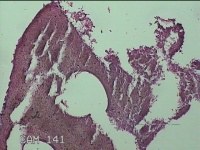

子宫颈管组织

性别

女

年龄

46岁

子宫腺肌症 子宫内膜增生 子宫内膜息肉?原发性不孕症

一般病史

月经不规则伴月经量多3年。

标本名称

大体所见

灰白暗红色不规则碎组织2x1.3x0.7cm一堆。